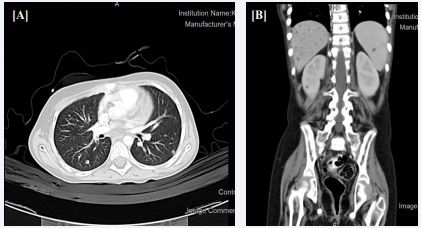

One and half year later the patient experienced severe febrile neutropenia. Initial fungal work up showed questionable lung nodules which could be fungal. Liposomal Amphotericin B was started and Caspofungin was discontinued. After about 4 weeks of severe fevers and neutropenia, a decision was made to give her G-CSF at 5 micgram/Kg/Day S/C. After 3 days her neutrophils count increased to >3000. Interim Maintenance I of Arm-C of the CALL08 Protocol started and she Vincristine IV, IT Methotrexate, IV Methotrexate and L-Asparginas was given. Two months later, the patient had severe neutropenia again with fevers and chills. CT chest, Abdomen and Sinuses showed numerous nodules of severe fungal infection with Invasive Aspergillosis in the liver, spleen and kidneys [Figure 1]. Patient also developed severe hyperbilirubinemia, but transaminases were normal. Total bilirubin increased to 464 and conjugated bilirubin was 181 & GGT to 1097.

Figure 1 (A) Chest CT scan chest showing tiny pulmonary nodules are noticed one in the left lower lung. (B) Abdominal CT with contrast of showing numerous nodules in the liver, spleen and kidneys.